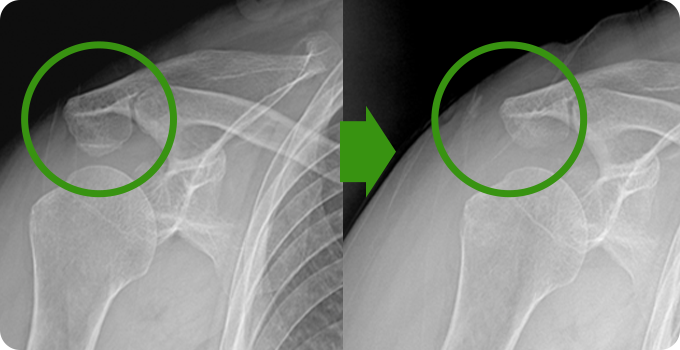

견봉성형술과 감압술은 어깨 관절의 충돌을 줄이고 통증을 완화하기 위한 수술적 방법입니다. 견봉성형술은 견봉의 아래쪽 뼈를 다듬어 회전근개와 견봉 사이의 공간을 넓히는 과정으로, 관절의 움직임을 개선합니다. 감압술은 염증을 유발하는 조직이나 점액낭을 제거하여 어깨 관절의 압력을 줄이고 기능을 회복합니다.